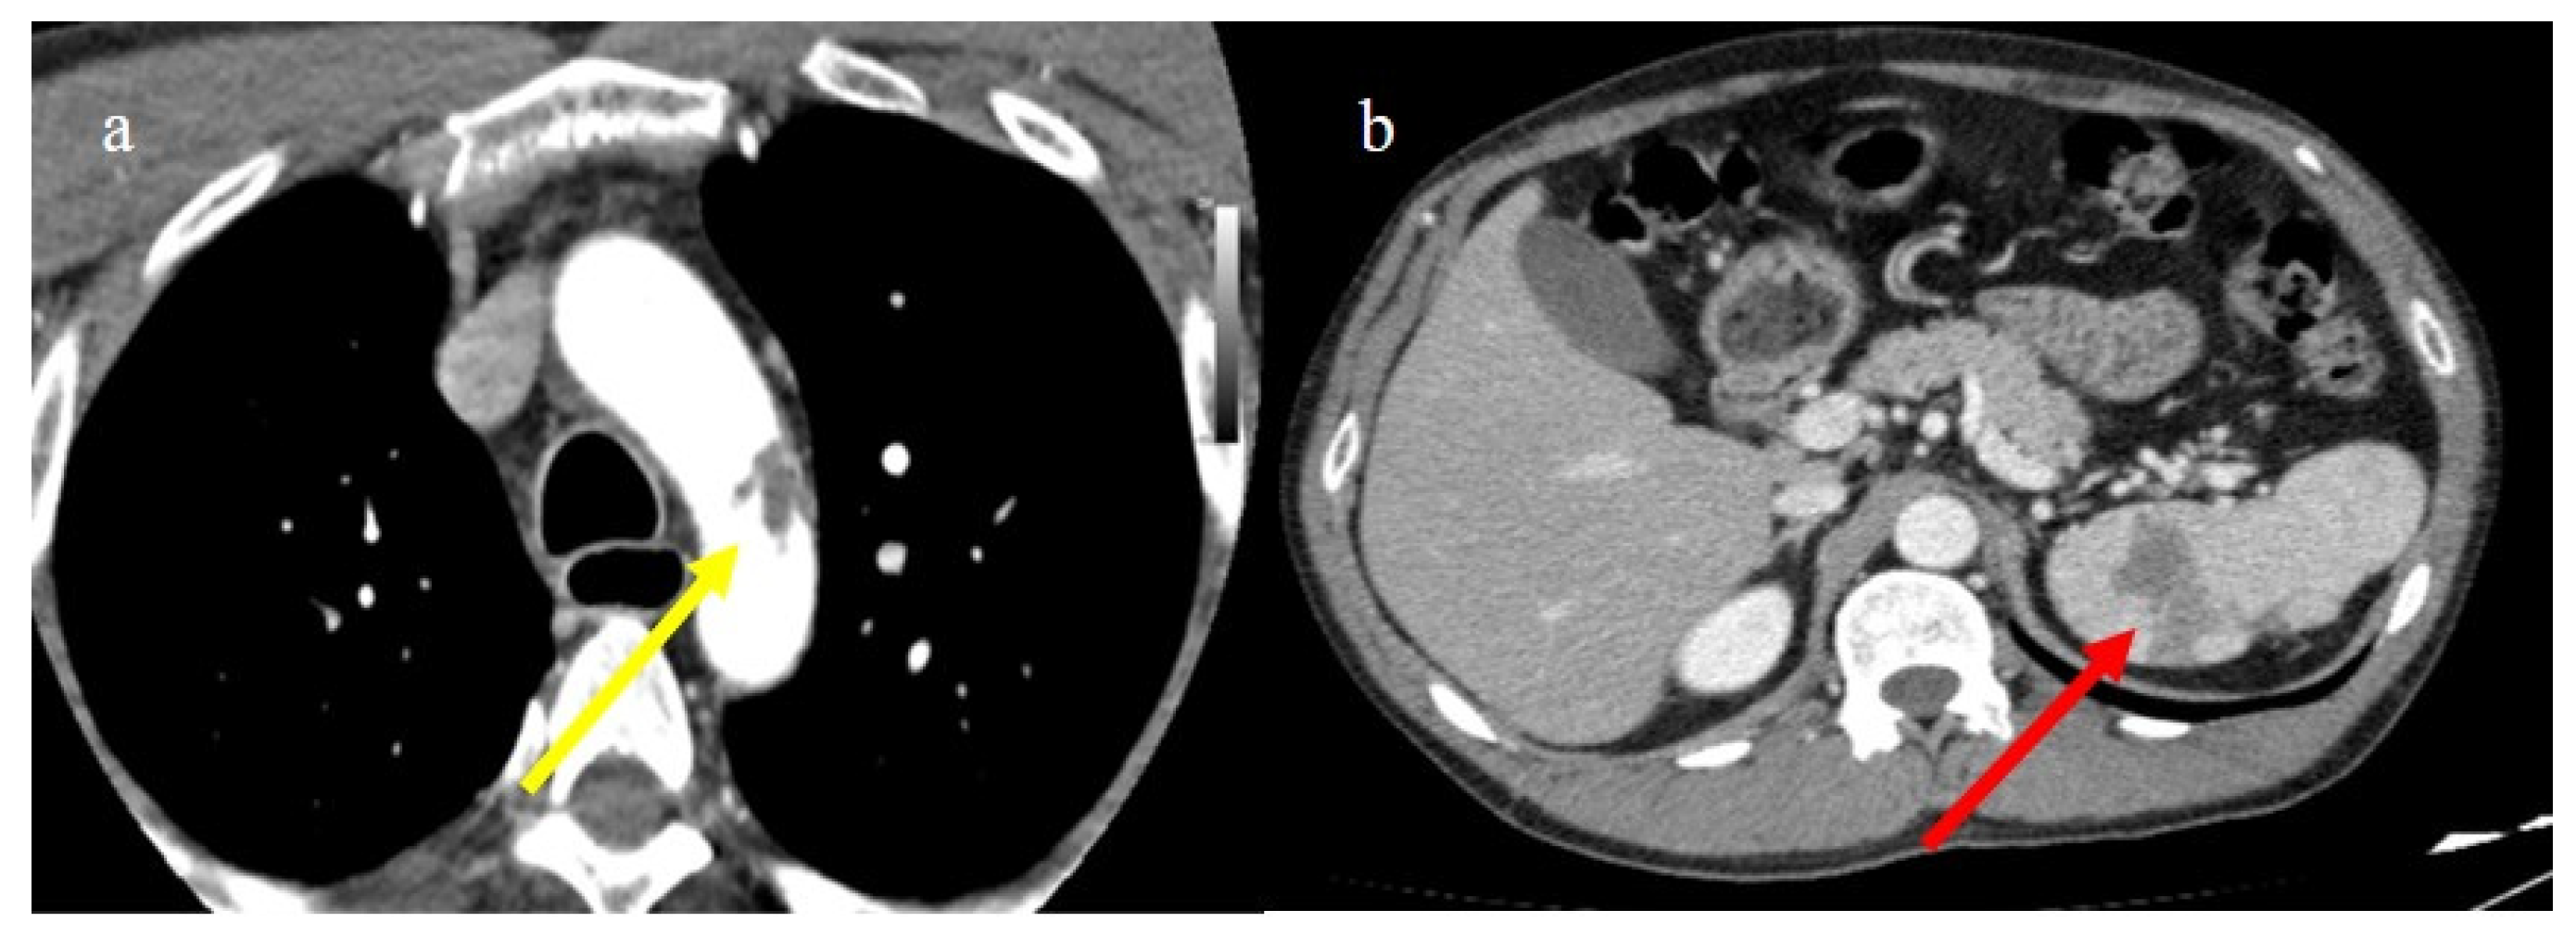

4. Vascular Abdominal Extrapulmonary Complications

4.2. Splenic and Renal Infarction

4.3. Hemorrhagic Abdominal Complications